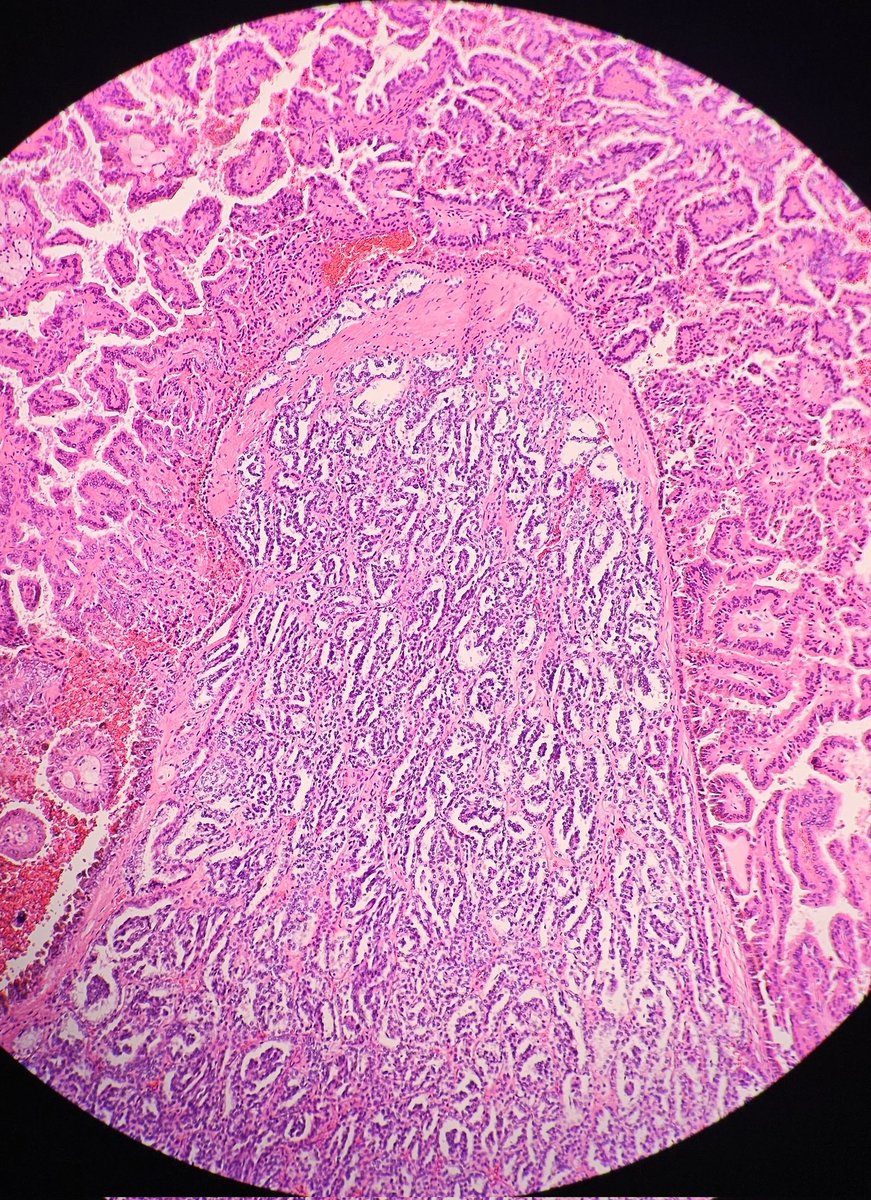

Papillary RCC showing type 1 and type 2 morphologies. #GUpath #pathology